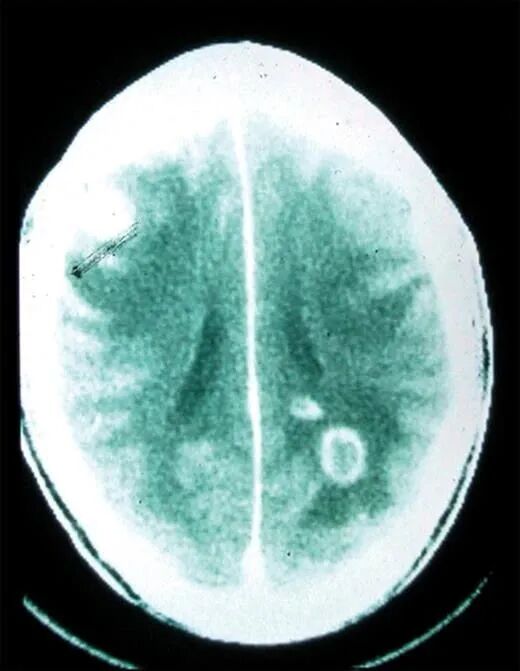

弓形虫感染人类大脑